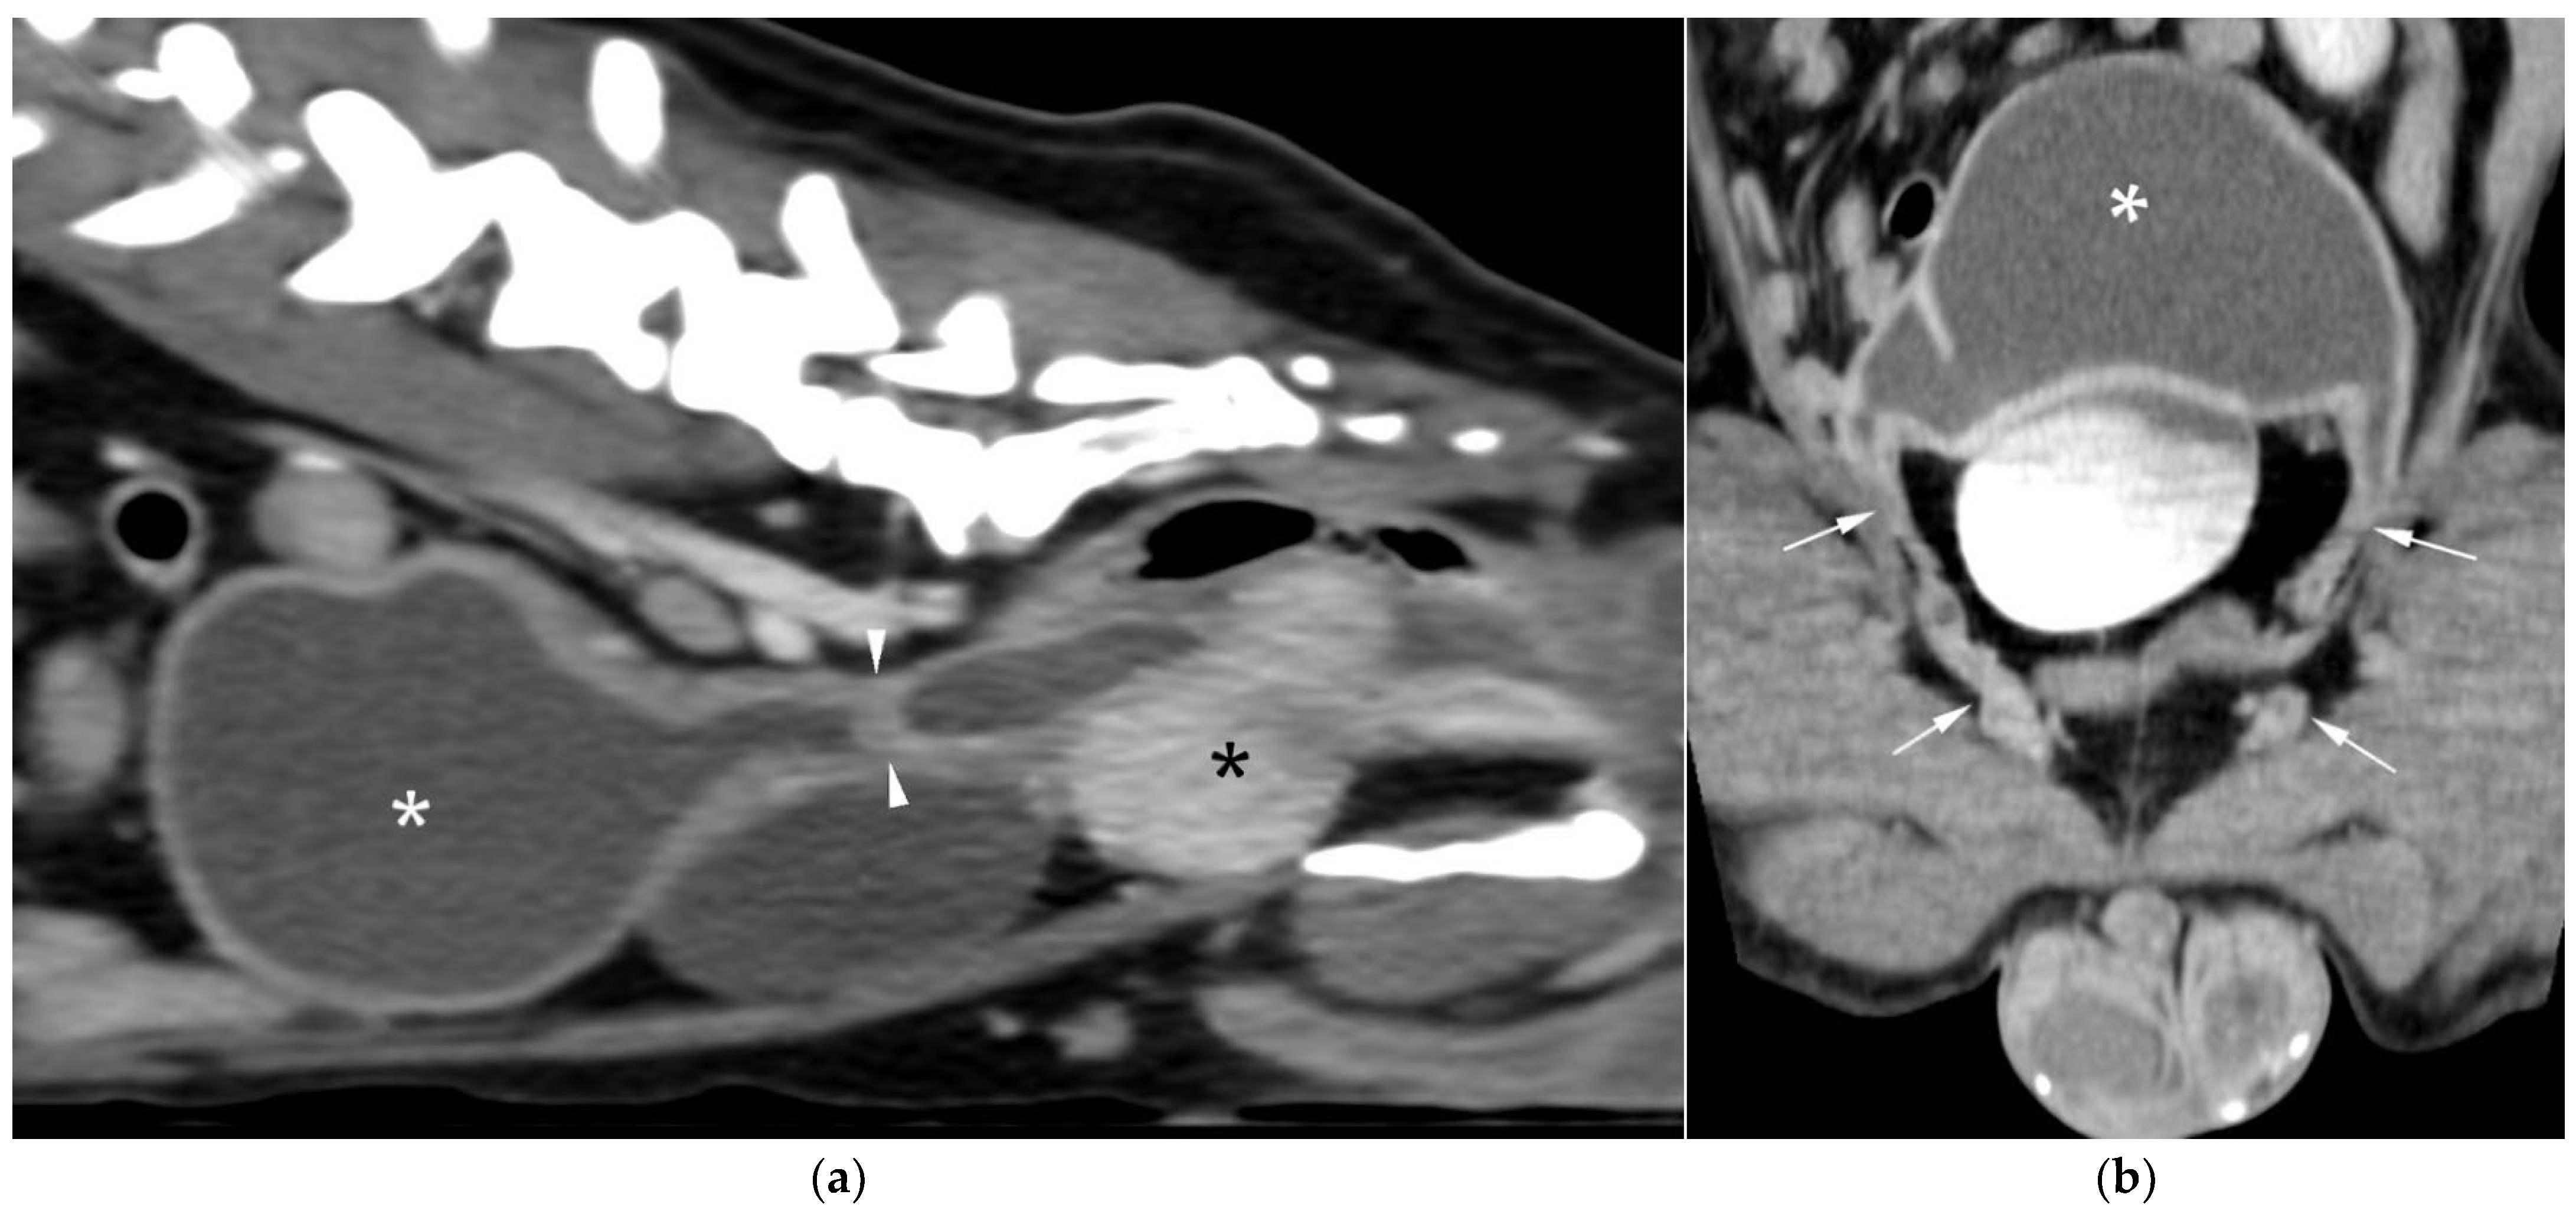

AUS in all three dogs revealed a fluid-filled cavitary structure originating in the caudal peritoneum between the colon and urinary bladder and extending cranially through the mid-abdomen, causing a mass effect. In cases 1 and 2, the lesion continued bilaterally as paired, thin tubular extensions coursing caudally through the inguinal rings adjacent to each testis (Figure 1a). In case 1, a focal mural narrowing resembling a uterine cervix was noted caudally (Figure 1b). The wall was thin and smooth in case 1, while in case 2 it was irregular, especially in its caudal aspect (Figure 2a,b). No information was available regarding the course of the UM horns or wall appearance for case 3. The luminal content consisted of echogenic, inhomogeneous fluid in all cases (Figure 3a); in case 2, sedimentation created fluid–fluid levels (Figure 3b).

Additional findings in all dogs included: enlarged, heterogeneous, cystic prostate; echogenic sediment in the urinary bladder; free peritoneal fluid [moderate and echogenic in case 2 (Figure 2a); mild and anechoic in cases 1 and 3]; and bilateral medial iliac lymphadenomegaly (moderate in cases 2 and 3; mild in case 1).

Figure 2. AUS of case 2: (a) Longitudinal view of the caudal UM, showing irregular wall margins (arrows), intraluminal inhomogeneous fluid, and free echogenic peritoneal fluid (arrowheads); (b) Detailed view of the UM wall demonstrating luminal irregular margins (arrows).

Figure 3. (a) AUS of case 1; transverse view of the most dilated UM segment containing inhomogeneous echogenic fluid; (b) AUS of case 2; oblique view showing two sections of the UM containing a moderate volume of sedimented material (asterisks), creating marked fluid–fluid levels.